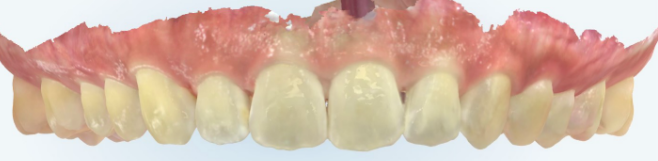

治療後の口腔写真

After

After